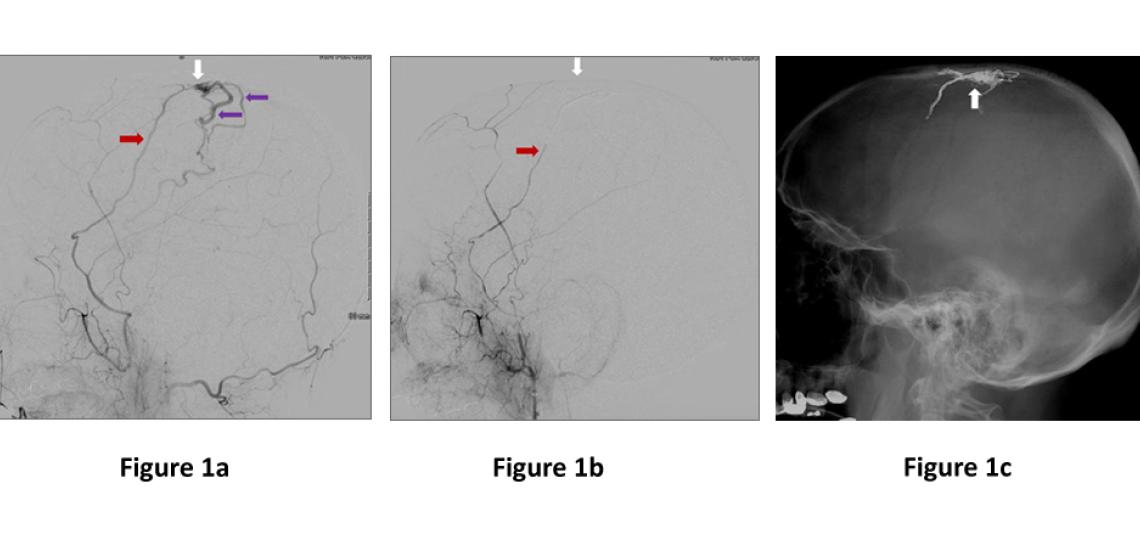

- Endovascular Embolization - This procedure entails passing a small catheter from a blood vessel in the groin up into the AVF, where glue or other material is injected into the abnormal vessel (Figure 1). This is the most common treatment of DAVF and is often curative.

Figure 1a: Lateral (side) view of a dural artery (red arrow) abnormally connecting to a large vein on the surface on the brain (white arrow), and high pressure arterial flow is immediately filling brain veins (purple arrows). Figure 1b. Immediately after embolization where glue was injected through the artery (red arrow) into the abnormal connection (white arrow) showing no more abnormal filling of the veins. Figure 1c. Lateral (side) view skull x-ray showing the glue material filling the area abnormal connection of the fistula (white arrow).